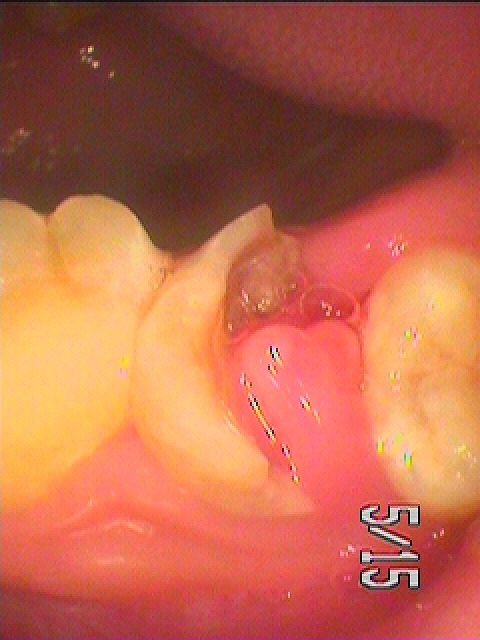

歯冠部がほとんど崩壊しており、8番もその穴へ傾斜しており難しい状態です

穴には歯肉も入り込んでいます

大きく歯肉も入り、7番は残す名がむつかしそうです

歯冠部に8番が大きくかぶさった状態になります

抜歯も難しそうです